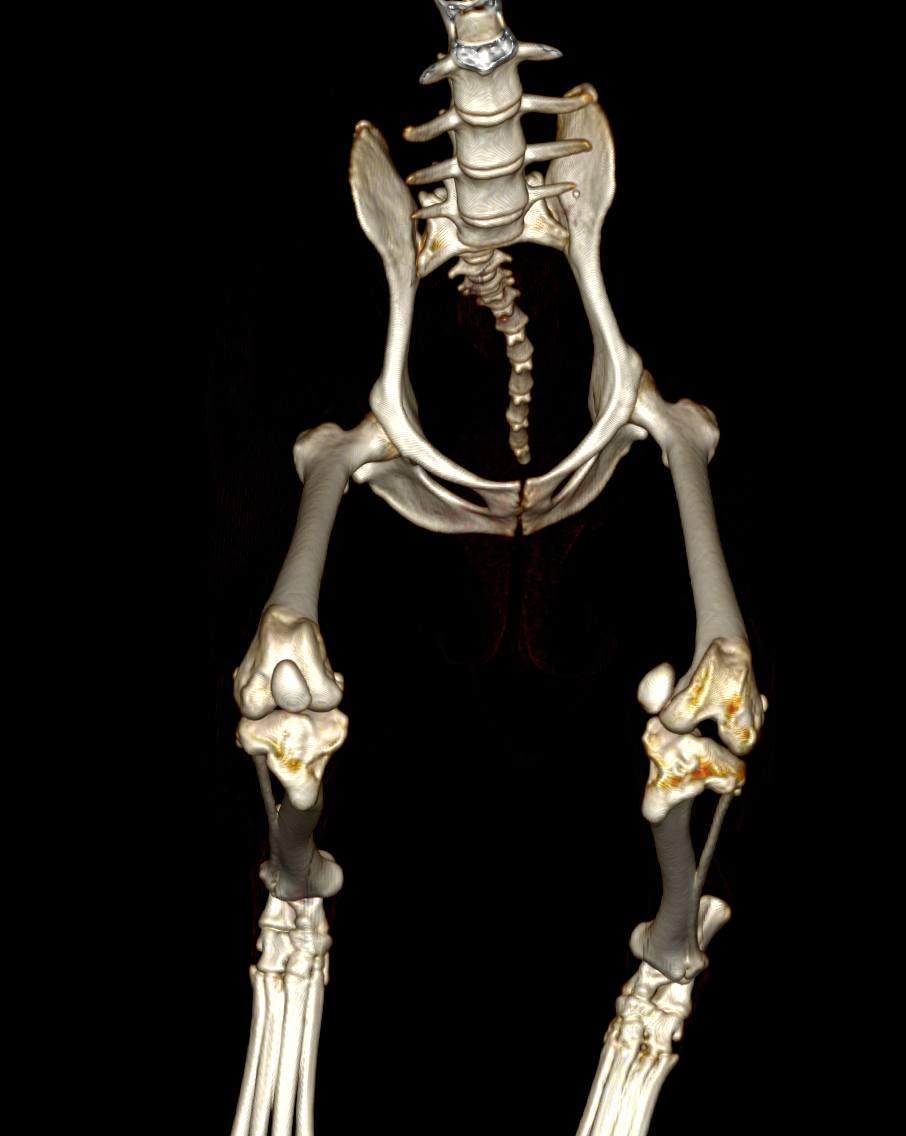

そのため、MPLグレード4の場合には手術の前にCT画像検査を実施し、大腿骨および脛骨と呼ばれる骨に変形がないかを確認します。レントゲンでも変形の評価はある程度可能ですが、3D的に変形していることが多いため、CT画像検査を実施しないと詳細がわからないことがほとんどです。

CT画像検査です。左のパテラ(向かって右側)は内側に大きく脱臼しています。この子の場合には大腿骨・脛骨共に大きな変形はないことがわかります。

この子は左右共にパテラが大きく脱臼しており、大腿骨・脛骨ともに大きく湾曲、回旋してしまっていました。